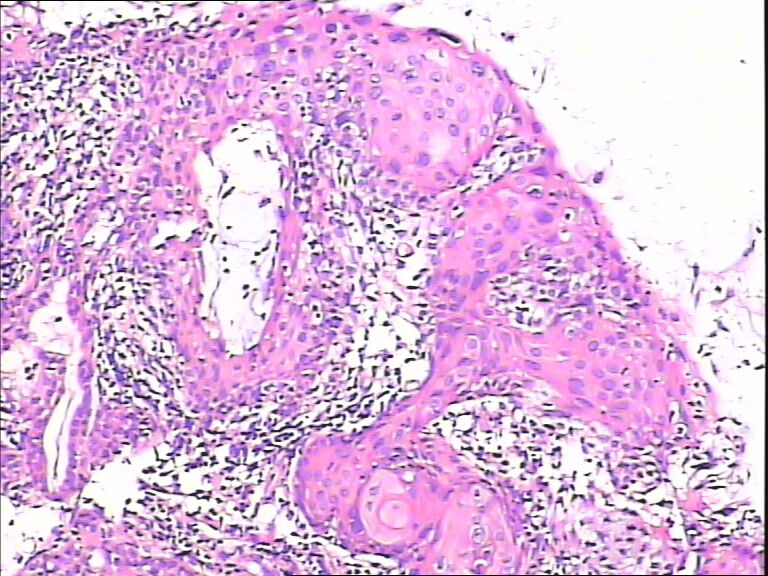

45y,触血,宫颈多点活检。